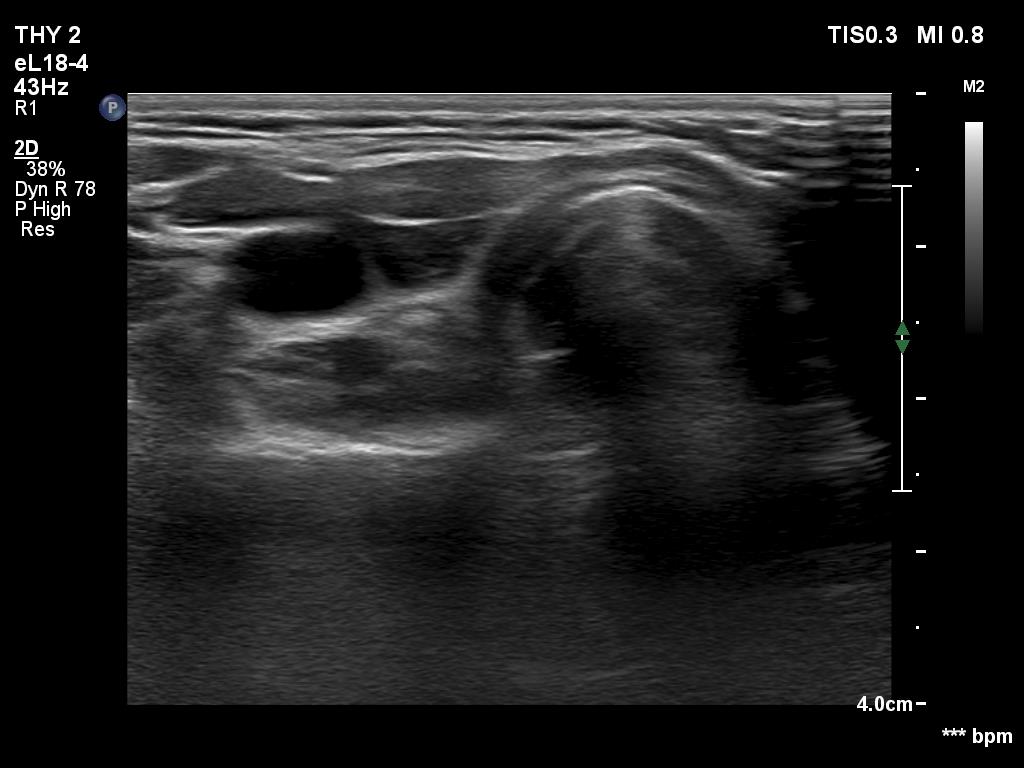

First examination (first two rows of images)

Clinical data: A 19-year-old woman came to a yearly follow-up examination. She has been operated on and has got radioiodine therapy for a T4 papillary cancer for six years. Two years after the surgery, a cystic lesion was found in the left thyroid bed with the diameters of 7x5x12 mm, width, depth and length, respectively. The largest diameter of the lesion ranged between 9 and 13 mm in the upcoming years, the thyroglobulin levels were always below 0.2 ng/mL.

Ultrasonography revealed a cystic lesion in the left thyroid bed. The dimensions of the cyst were 8x6x13 mm, width, depth and length, respectively.Suggestion: to continue with the daily 125 microgram levothyroxine. TSH in a year, in the event of pregnancy at once.